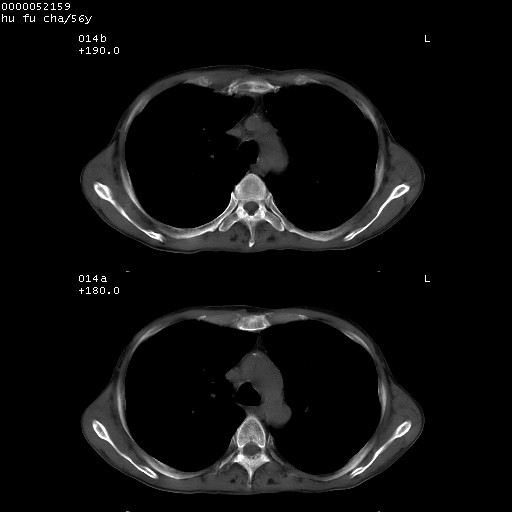

以下是引用zsl6918在2008-8-25 22:47:00的发言:[br]胸骨,胸椎及肋骨均可见多发转移表现,肝内低密度结节不除外转移。原发灶可能在右肺。双侧可见支扩表现。

以下是引用宇宙ct在2008-8-25 23:26:00的发言:[br][br] 胸骨,胸椎及肋骨均可见多发转移表现,肝内低密度结节不除外转移。原发灶可能在右肺。双侧可见支扩表现。 [br] [br]

以下是引用卜一在2008-8-26 8:02:00的发言:[br][br] 支持:肺癌并肺内,胸骨,胁骨,胸椎及肝内转移!另:左肺支气管扩张征伴感染! [br]

以下是引用zjzjr在2008-8-26 11:03:00的发言:[br]支持:肺癌并肺内,胸骨,胁骨,胸椎及肝内转移!另:左肺支气管扩张征伴感染!